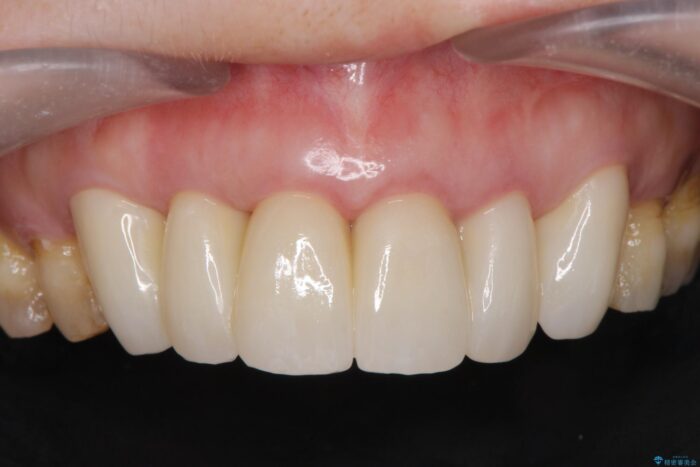

この状態で再度セラミッククラウンの作製・装着を行ってもまた同じ状態となってしまうため、歯周外科を行い歯ぐきの状態を整備したのちセラミッククラウン治療をおこなっていきます。

治療後について

治療には歯肉を成熟させる期間を含めて約8ヶ月間要しましたが、出血や違和感のない歯ぐきとなり大変ご満足いただけました。